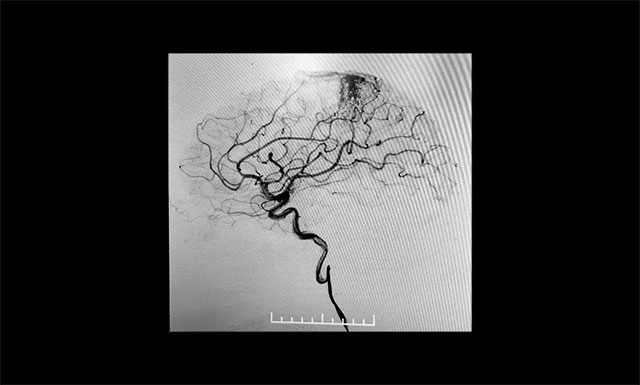

▲ DSA檢查顯示,中央后回動(dòng)靜脈畸形

患者為55歲男性,4月份突發(fā)右眼失明,頭顱CT+CTA顯示,左側(cè)頂葉異常強(qiáng)化灶,考慮血管畸形AVM可能。經(jīng)醫(yī)院DSA檢查,確診為功能區(qū)動(dòng)靜脈畸形,畸形團(tuán)分布較彌散,位于中央后回,主要由大腦前動(dòng)脈分支供血,通過皮層靜脈向上矢狀竇引流。該患者畸形血管團(tuán)體積較大,且與其相連的供血?jiǎng)用}及回流靜脈交織紛亂、復(fù)雜、異常粗大,病灶緊鄰運(yùn)動(dòng)中樞、語言中樞、書寫中樞等重要結(jié)構(gòu)。